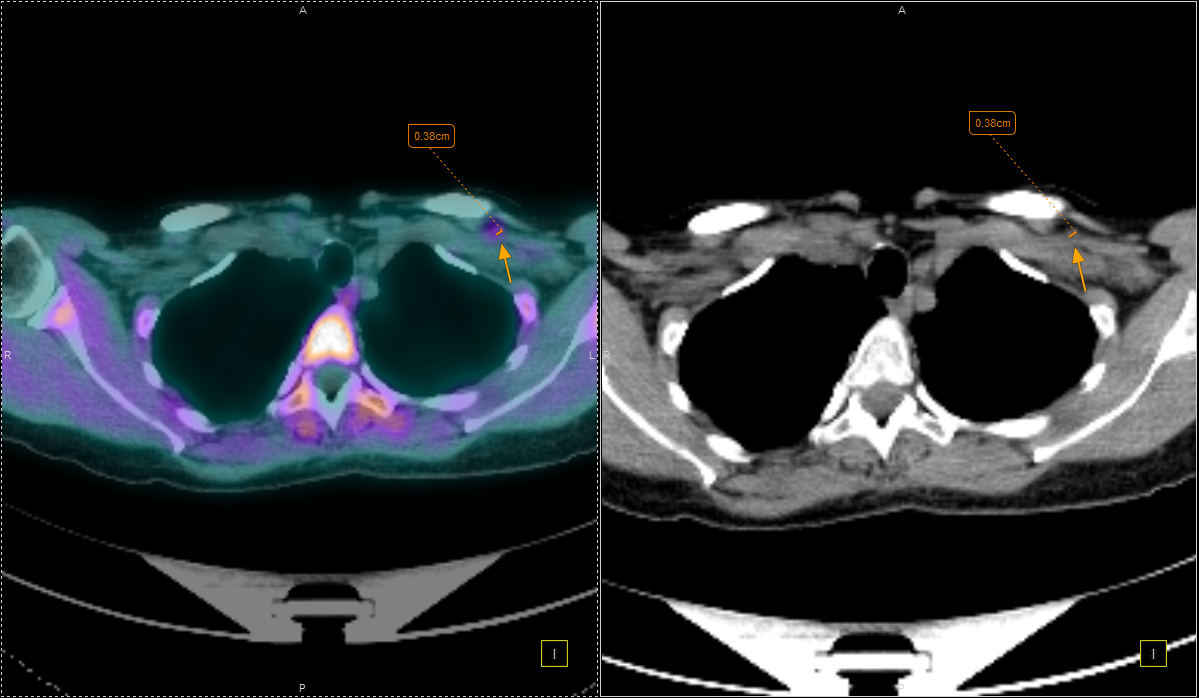

Η Τομογραφία Εκπομπής Ποζιτρονίων (PET) αποτελεί μια εξειδικευμένη μέθοδο της Πυρηνικής Ιατρικής που χρησιμοποιεί μοριακή απεικόνιση για να εντοπίσει και να παρακολουθήσει φυσιολογικές και παθολογικές λειτουργίες του οργανισμού. Συνδυάζοντας τη λειτουργική απεικόνιση της PET με την ανατομική πληροφορία της αξονικής τομογραφίας (CT), η υβριδική εξέταση PET/CT παρέχει εικόνες υψηλής ευκρίνειας και τη δυνατότητα ποσοτικής αξιολόγησης των βιολογικών μηχανισμών σε κυτταρικό επίπεδο.

Η PET/CT αποτελεί εξαιρετικά προηγμένη τεχνική της σύγχρονης ιατρικής απεικόνισης και χρησιμοποιείται τόσο για τη διάγνωση όσο και για την παρακολούθηση της ανταπόκρισης στη θεραπεία.

Με τη χρήση ειδικού λογισμικού Τεχνητής Νοημοσύνης (MIM – Lesion ID) πραγματοποιείται αυτόματος υπολογισμός της έκτασης και του όγκου των θέσεων ενεργού νόσου. Ξεπερνώντας τις δυνατότητες του ανθρώπινου οφθαλμού υπολογίζεται το συνολικό φορτίο νόσου πριν και μετά την θεραπεία επιτρέποντας ακριβέστερο χειρισμό του ασθενούς από τον θεράποντα ιατρό.

Στο Κέντρο PET/CT πραγματοποιούνται εξειδικευμένες εξετάσεις που καλύπτουν ένα ευρύ φάσμα κλινικών εφαρμογών στη σύγχρονη Πυρηνική Ιατρική. Ανάλογα με το είδος του προβλήματος και τη φύση της νόσου, χρησιμοποιούνται διαφορετικά ραδιοφάρμακα για τη μελέτη συγκεκριμένων βιολογικών μηχανισμών.